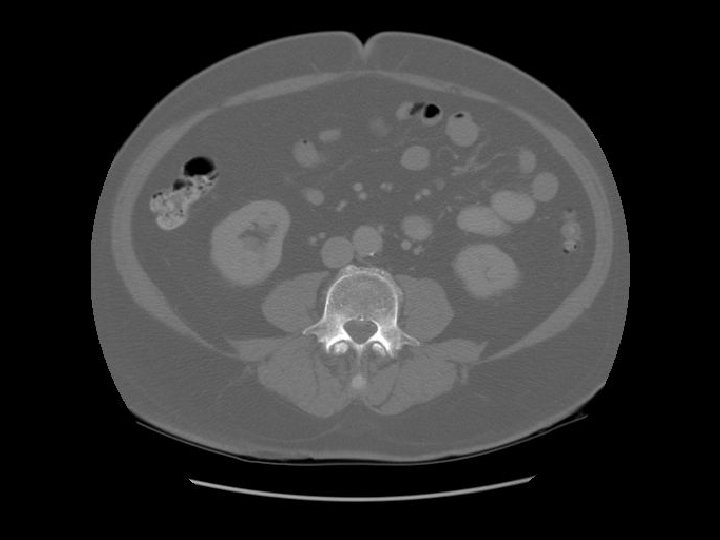

Abdominal aorta about to bifurcate.

Psoas

Rt common iliac artery IVC Lt common iliac artery

L 5

Arrows are pointing to the common iliac veins joining to form the IVC. Left